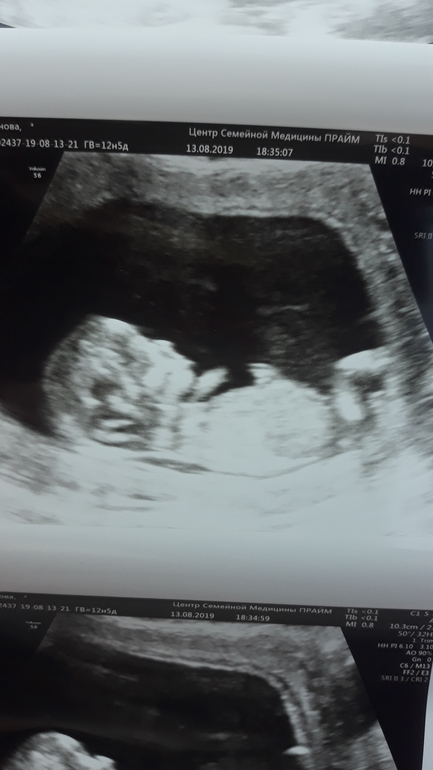

Девченки кто может помочь определить пол,обещают мальчишку а до 2го узи еще месяц ждать.

на 3й фотографии тоже не понятно что там у него кокички или писюшка🤣